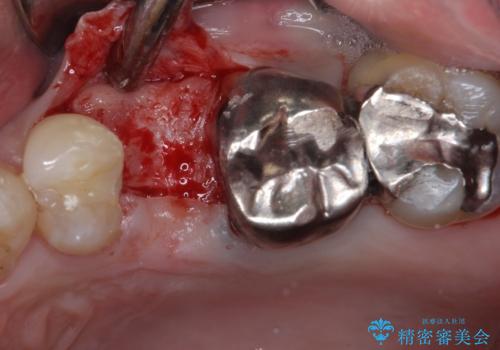

歯肉の中、深いところまでむし歯が進行しており、歯根を部分矯正で引っ張り出してから補綴治療を行うか、抜歯してインプラント補綴治療を行うか選択することになりました。

海外での勤務があり、部分矯正は困難とのことで、インプラントによる補綴治療を行うこととしました。

インプラントは、骨との生着能が比較的高いとさせるSLAタイプを使用しました。